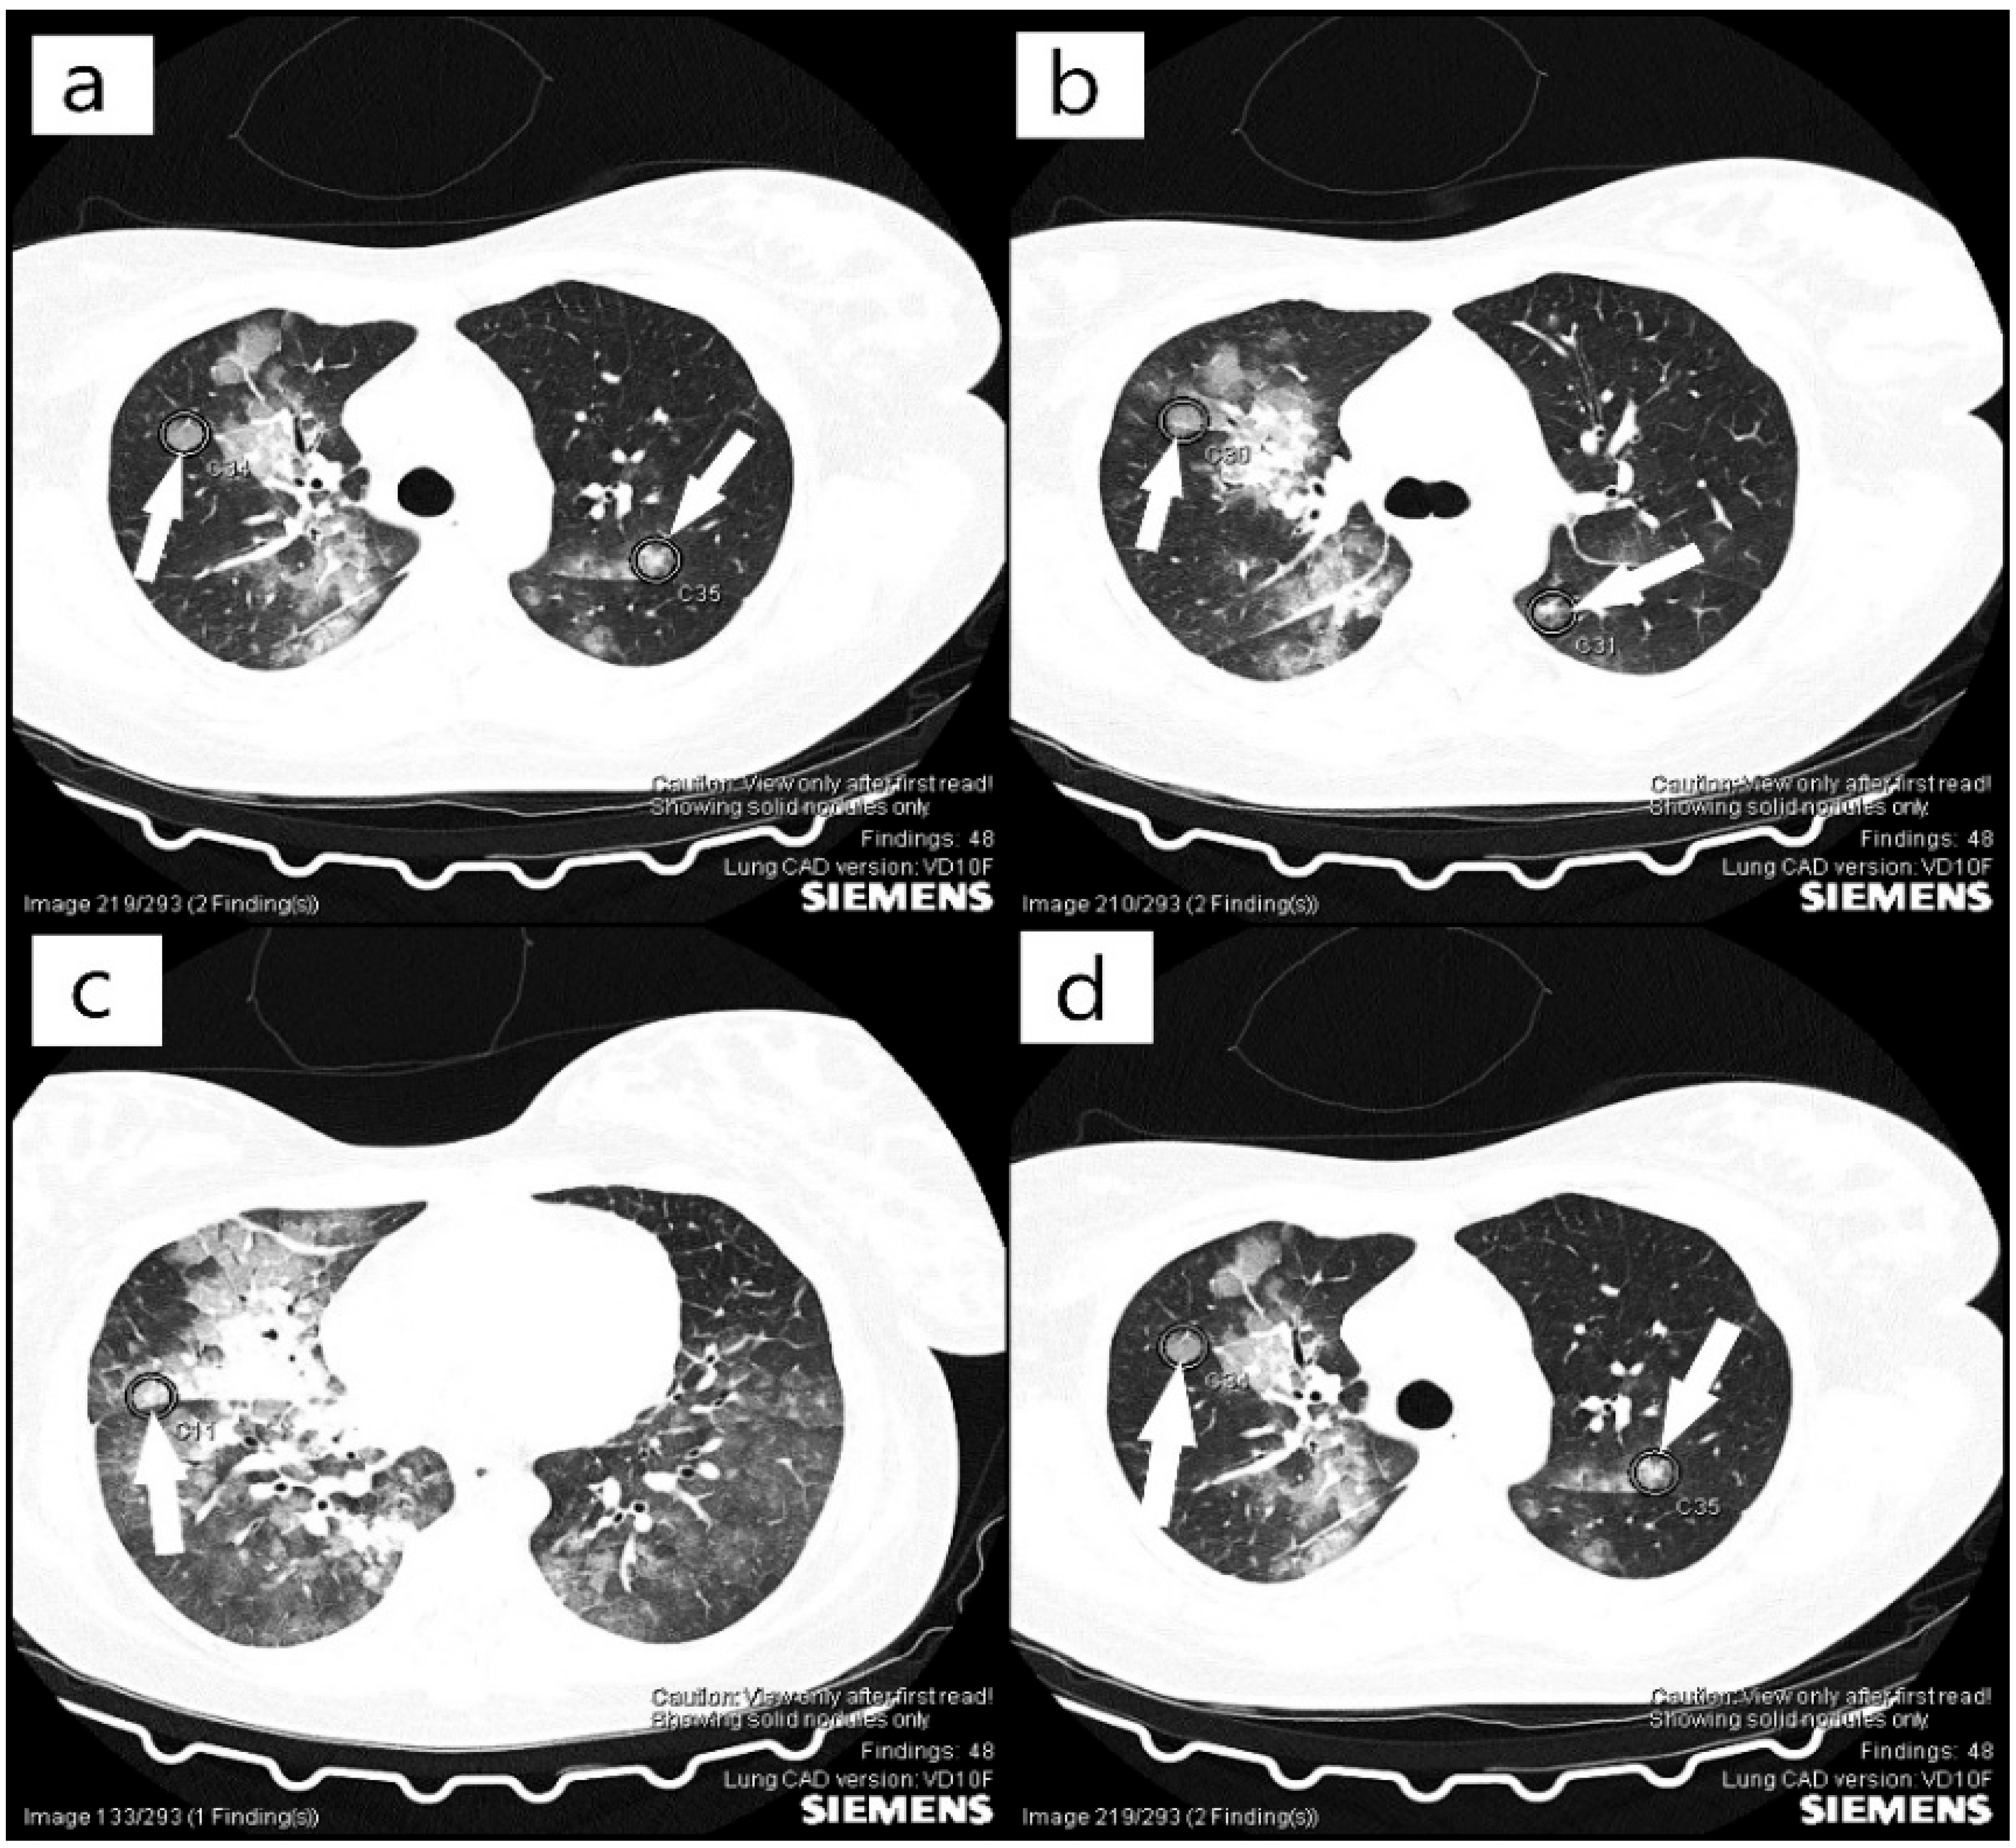

2. Case Report